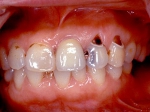

インセラム(オールセラミック)冠による修復。 主訴は前歯が汚い 金属を使わないオールセラミックでの治療を勧めた。 術前

術後